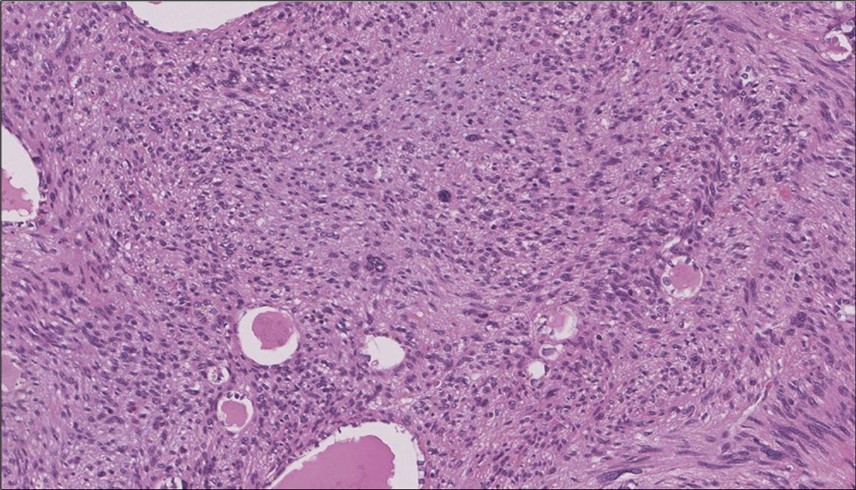

When diagnosing thyroid swelling, imaging studies have been helpful in differentiating malignant from benign tumors with US being used as an initial evaluation tool when assessing thyroid nodules. Tumors are categorized based on composition, echogenicity, shape, margin and echogenic foci into added scores determined by the TI-RADS system, which determines the need for FNA 13. Other imaging modalities include MRI and CT. However; radiological assessment does not distinguish between the types of thyroid cancer, and therefore FNA and biopsy are of crucial importance 3, 6. On a pathologic sample, LMS appears as spindled eosinophilic cells with elongated blunt-ended or cigar-like nuclei arranged in fascicles 2, 7 (Figure 1, Figure 2, Figure 3). Despite the unique microscopic morphology, LMS cannot be distinguished from other spindle cell tumors such as spindle cell variant of medullary thyroid cancer, anaplastic thyroid

Figure 2.Left thyroid On a Higher power, few thyroid follicles are noted and the lesion is composed of spindle cells with sweeping fascicles (H&E, ×200).

Figure 3.Left thyroid The malignant looking cells are showing diffuse atypia, mitosis and hyper-chromatic nuclei, some remaining follicles could be noted as well (H&E, ×400).

cancer, or other metastatic tumors without further testing with genetic or molecular studies 3, 7. Immunohistochemical testing plays a vital role in differentiating LMS from such similar tumors as it stains positive for vimentin and smooth muscle actin (SMA), and is variably positive for HHF35, desmin (50%-100%), and H-caldesmon 3, 6. Moreover, there were no reported cases where thyroid LMS stained positive for thyroglobulin, cytokeratin, calcitonin, chromogranin, or protein S100 3. Our patient’s left thyroid biopsy showed the characteristic microscopic features and was positive for SMA, desmin, caldesmon, P63 with patchy EMA (Figure 1, Figure 2, Figure 3, Figure 4) as well as her liver biopsy (Figure 5, Figure 6, Figure 7); whereas her right thyroid showed clear papillary thyroid cancer cell features (Figure 8, Figure 9).